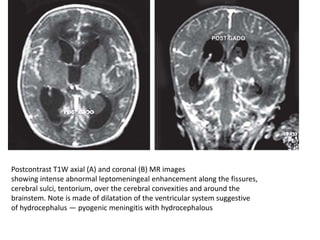

Postcontrast T1W axial (A) and coronal (B) MR images

showing intense abnormal leptomeningeal enhancement along the fissures,

cerebral sulci, tentorium, over the cerebral convexities and around the

brainstem. Note is made of dilatation of the ventricular system suggestive

of hydrocephalus — pyogenic meningitis with hydrocephalous

• On contrast enhanced CT scan, there is

enhancement of the inflammatory exudate in

the involved basal cisterns, fissures or sulci

• The abnormal leptomeningeal contrast

enhancement is typically more readily

apparent and more intense on MR imaging

rather than on CT scanning.